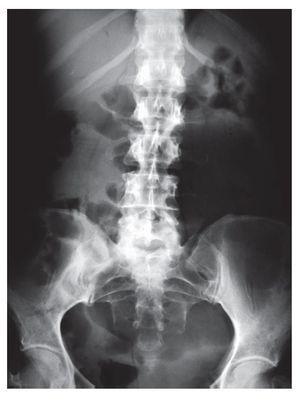

Paciente femenino de 46 años de edad, sin patológicos de importancia portadora de estreñimiento crónico de 26 años de evolución con autoprescripción. Inicia con dolor abdominal súbito de 2 días de evolución localizado en cuadrante inferior izquierdo, tipo cólico, sin náusea ni vómito, por lo que ingiere pancreatina con dimeticona sin mejoría, incrementando el dolor y agregándose náuseas, distensión abdominal e imposibilidad para canalizar gases, motivo por el cual acude a valoración. A su ingreso con vitales normales, con fascies de dolor, actitud forzada por dolor abdominal, mesomórfica. Mucosas parcialmente hidratadas, pálidas, cardiopulmonar sin alteraciones. Abdomen distendido, blando, doloroso a la palpación media y profunda de predominio en cuadrante inferior izquierdo, sin hiperestesia ni hiperbaralgesia. Rebote negativo. Peristalsis de lucha. Extremidades sin alteraciones. En radiografías simples de abdomen se observa distensión importante de colon proximal con nivel hidroaéreo en colon transverso y ausencia de gas en colon descendente y ámpula rectal (Imágenes 1 y 2). Se realiza colonoscopia con diagnóstico inicial de obstrucción colónica, introduciendo colonoscopio hasta una distancia de 120 cm, con lo que se llega a tercio distal de colon transverso impidiendo avanzar más el endoscopio por una zona de estenosis puntiforme, probablemente secundaria a torsión (Foto 1) intentando realizar detorsión sin éxito, por lo que es sometida a laparotomía exploradora encontrando torsión de colon transverso (Fotos 2 y 3) efectuando hemicolectomía derecha con transversectomía e ileosigmoideoanastomosis con engrapadoras, con una evolución favorable, siendo egresada al cuarto día por mejoría.

Imagen 2. Placa simple de abdomen en decúbito.